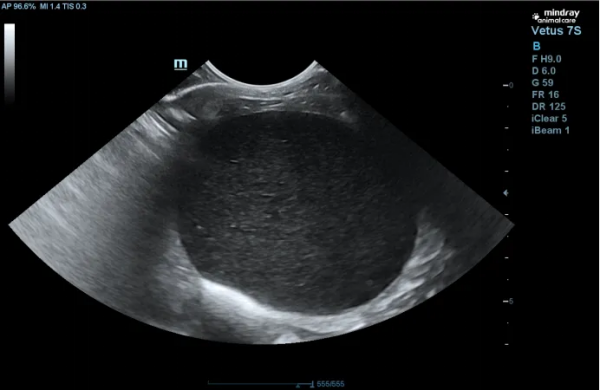

一、引言 猫下泌尿道综合征(Feline Lower Urinary Tract Disease,简称FLUTD)是一种常见的猫病,主要表现为猫出现尿频、尿急、尿道炎症等症状。这不仅会给猫带来疼痛和不适,还可能威胁到猫的生命安全。 FLUTD的发病原因复杂,可能与猫的饲养环境、饮食习惯、生理状况等多方面因素有关。一些可能造成FLUTD的风险因素包括:高镁、高蛋白饮食、缺水、缺乏运动等。情绪压力、尿道感染、膀胱结石等因素也可能引发FLUTD。 识别FLUTD的症状对及时治疗和预防疾病的进展至关重要。常见的FLUTD症状包括:频繁去猫砂盆、尿中带血、尿液颜色浑浊等。一旦发现猫出现以上症状,主人应及时就医,进行诊断和治疗。 了解FLUTD并且采取预防措施是非常重要的。通过合理的饮食管理、保持适当的水分摄入、定期检查和观察猫的排尿情况等方法,可以有效预防FLUTD的发生,保护猫咪健康。希望本文的内容能帮助更多的猫主人了解并识别FLUTD,及时治疗,减轻猫咪痛苦。 二、基本信息 蓝猫,年龄:1岁6月,公,绝育,疫苗完全,驱虫完全,体重:5.5kg 病史:2025年3月到2025年7月18日期间,该猫反复出现尿频、尿闭,共治疗过4次,近日主人又发现猫咪频繁去猫砂盆,但是未见尿液排出,精神状态萎靡,食欲减退。遂带来本院治疗。 三、检查项目及结果 体格检查:背毛粗糙,皮肤弹性尚可,未见脱水,黏膜皮肤颜色正常,瞳孔反射正常,步态正常,体温38.1℃,体重5.5kg,听诊心率心音正常,触诊体表淋巴结未见肿大,双肾大小基本一致。但在触诊至膀胱区域时,猫出现明显不适,膀胱充盈,坚实。视诊腹部未见明显膨大,生殖器红肿。 化验室检查: 血常规 结果:血常规检查结果无异常 2.生化检查 结果:生化结果显示,该猫肌酐和尿素氮指标显著升高。 3. B超检查 结果:B超扫查发现,膀胱充盈,膀胱壁欠光滑,腔内充满产回声内容物,提示膀胱内有泥沙样结晶。 四、诊断结果 综合上述检查结果,引起该猫出现尿闭的原因应为:膀胱内结晶引起的猫下泌尿道梗阻。 五、治疗方案及预后 治疗方案: 1、导尿:该猫膀胱充盈,无法自主排出尿液,故紧急进行导尿,并进行导尿管留置,方便后续观察尿液情况。 2、膀胱冲洗:该猫导尿后就办理了住院,因膀胱内大量结晶,为防止结晶再次阻塞尿道,遂每日采用温热的无菌生理盐水对该猫膀胱进行冲洗,减少膀胱内结晶。 3、输液治疗:该猫导尿后,精神有所恢复,有食欲,故在住院治疗期间,只选择使用了乳酸林格进行补液。 该猫入院48h后,情况稳定,精神食欲恢复,尿液颜色正常,遂拆除导尿管观察。第三天,观察到猫咪能够自主去猫砂盆排尿,尿量正常。主人也因费用问题,选择将猫咪接回家护理。 4、口服药:膀胱黏膜修复剂:冀苍蓝,每天2袋; 化结晶药物:尿石消每天1粒; 抗生素:克维舒干混悬剂:1ml/猫,BID 一周后主人带猫来复查,猫咪已经好转,在家排尿正常。又拿一周的尿石消和冀苍蓝进行巩固治疗。半月后该猫再次复诊,B超扫查发现膀胱恢复良好,主人拒绝血常规和生化检查。 六、讨论及小结 此病例为膀胱内结晶引起的猫下泌尿道梗阻,采用了导尿、膀胱冲洗,输液等常规治疗方案进行治疗后,此病例基本痊愈。复盘整个病例,发现几点不足:一是没有对尿液进行尿常规检查,缺乏对尿液性质的评估;第二,未对膀胱内结晶进行检查分析,不知道该猫咪膀胱内结晶为哪种类型的结晶,如果做了结晶分析,能够为后续选择药物和家庭饮食方案制定提供更有效的建议,降低复发率。第三,根据猫泌尿系统疾病指南,猫膀胱炎多为无菌性疾病,在此病例中,血常规结果亦无明显提示,故没有使用抗生素的必要。但在该病例中,我使用了阿莫西林克拉维酸钾进行治疗,是基于几点考虑:1、对该猫进行了导尿治疗,并留置了48h,为防止出现逆行性感染(指南中也指出导尿管留置会有30%的可能性出现逆行性感染),故使用抗生素进行了预防性治疗。2、使用抗生素前,曾对主人提及建议做药敏试验,但主人出于费用问题考虑,未接受建议。故在未做药敏试验的情况下,选择使用广谱抗生素阿莫西林克拉维酸钾。该猫喂药较为困难,所以选择适口性更好的克维舒干混悬剂进行口服,猫咪更易接受且不容易应激。 经过此次病例复盘,之后再遇到类似病例,会更全面的考虑问题,将尿液检查作为重要的检查项目,会更规范的进行操作,尽量避免在此类病例中使用抗生素,如需使用,也会在药敏试验结果指导下进行合理使用。 七、参考文献 [1]夏兆飞等主译\(美)RICHADW.NELSON等主编.小动物内科学(第三版)[M].北京: 中国农业大学出版社,2012:1015-1016,770-774. [2]小动物临床手册(第四版)/(美)RheaV.Morganz主编;施振声主译 [3]犬猫解剖学彩色图谱/StanleyH.DonePeterC.GoodySusanA.EvansNell C.Stickland著;林德贵、陈耀星主译。